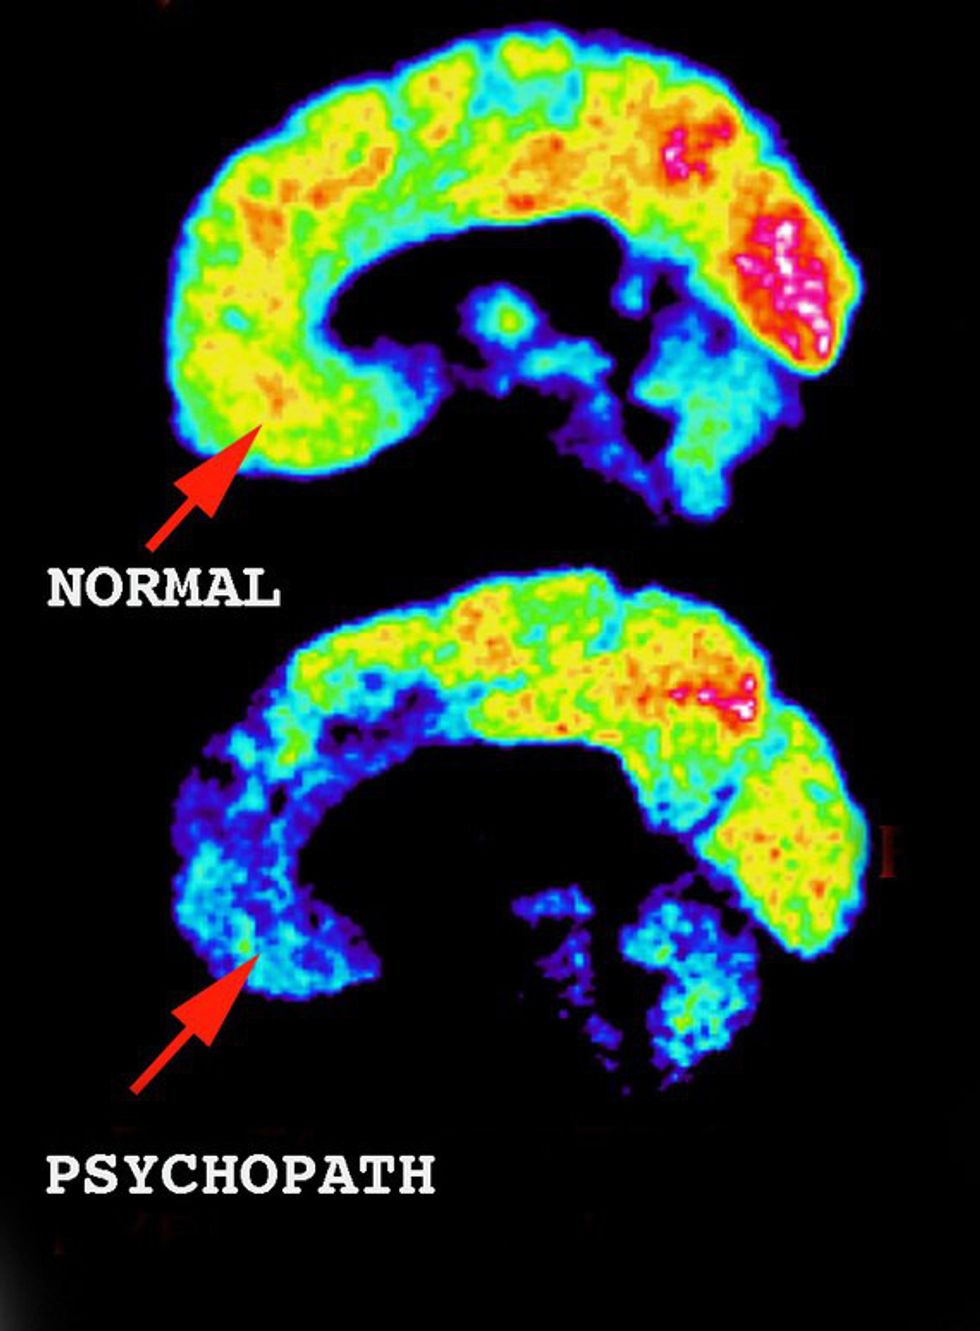

7. There are structural and functional abnormalities in the brain regions of psychopaths that are involved in emotional processing.

Brain imaging studies have shown that there are abnormalities in the regions that control empathy, regret, reasoning, recall of emotional memories, and fear.